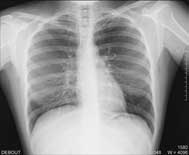

une radiographie du Thorax qui permet |

| d’apprécier l’état des poumons |

| d’apprécier la taille du cœur et du médiastin |